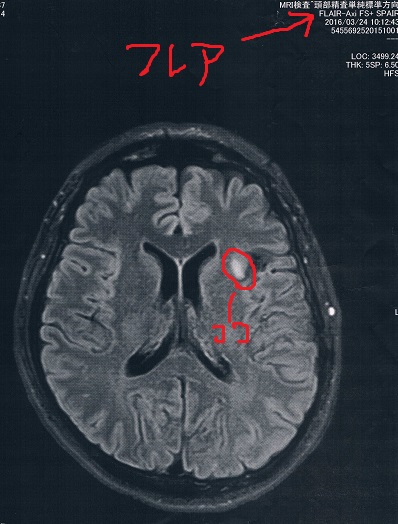

今回2016/3/24(手術後21か月)のMRI画像

今回もらった画像は前回とは画像強調が異なっているので白黒が反転しているところがある。

が、問題の腫瘍の部分は変化が無いので問題なし!

(興味ある人はFLAIRとT2で検索すると、MRIに詳しくなれます。)